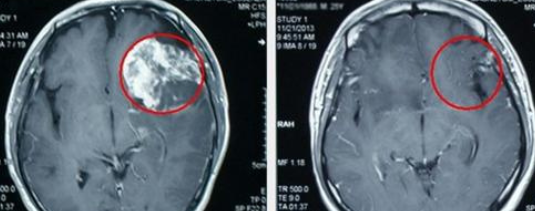

INC国际神经外科医生集团旗下组织国际神经外科顾问团成员、国际颅底肿瘤手术教授巴特朗菲教授表示,对于复发的胶质瘤患者,治疗方法主要还是手术、放疗、化疗。手术依然是主要治疗手段,即使再次手术往往更加棘手,存在着更大的风险。手术可以明显延长患者生存期,好转患者生存质量,减轻肿瘤负荷,还可为进一步治疗创造条件。再次手术切除复发脑胶质瘤的时候,同样是在保留重要神经功能的前提下,尽量多切肿瘤,降低颅内压力,减轻肿瘤对重要组织及神经的压迫,及保障患者的生活质量放在首位。

对于再复发的胶质瘤患者,巴特朗菲教授表示,在显微外科手术下结合术中核磁、神经导航等现代化高复杂设备辅助下,巴特朗菲教授也有信心为其成功切除,并且能尽可能的在避免损伤脑组织的情况下,进行90%以上高切除率的手术。